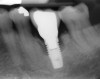

The resolution of the inflammatory aspect of the peri-implantitis lesion (Figure 26) was evidenced by 3-mm pocketing and an absence of bleeding upon probing. A 17-month follow-up (Figure 27) demonstrated resolution of the mucogingival problem, as evidenced by a deepened buccal vestibule, a zone of keratinized gingiva, and correction of the recession. A 17-month post-treatment radiograph (Figure 28) showed bone fill with elimination of the infrabony component of the lesion. Even with the close bone-to-implant approximation evident, a claim of osseous regeneration cannot be validated without histologic verification.

Fig 28. Seventeen-month post-treatment radiograph demonstrating bone close to the implant approximation and almost complete osseous fill of the original infrabony defect.

Figure 28